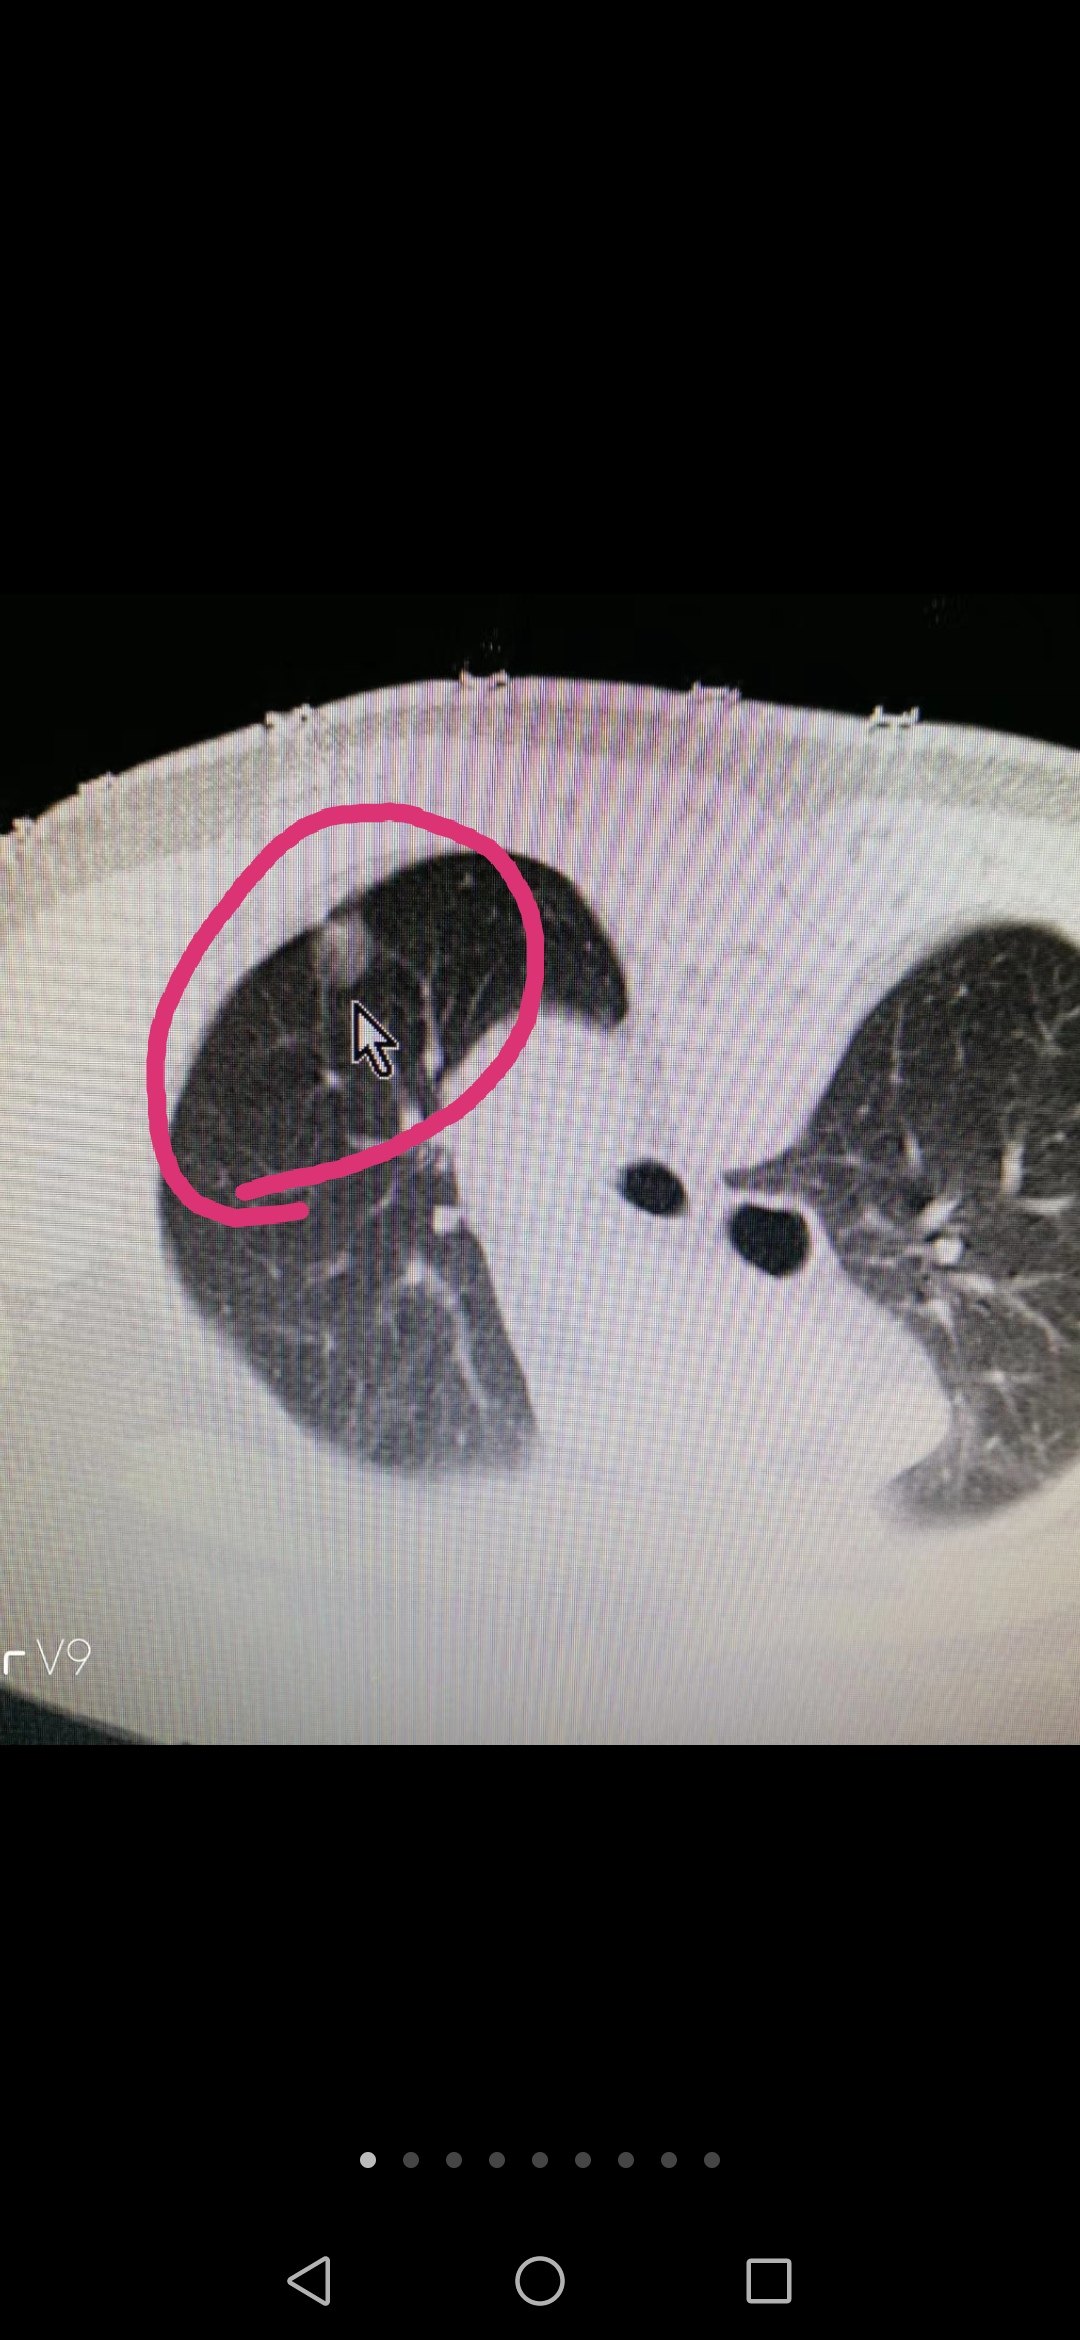

Screenshot_20200119_081045.jpg

图片里面的肺部小结节经过微创手术切除后经病理检查证实为:肺部“微侵润性腺癌”。